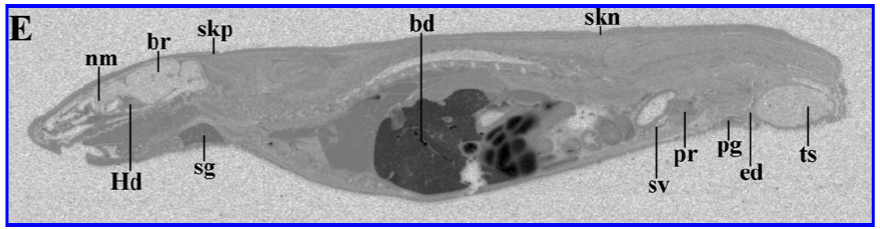

| Figure 2: Whole-body autoradiogram of a male rat 4 hours after a single oral administration of [14C]-Remogliflozin etabonate at a dose of 10 mg /kg in 0.5% (w/v) aqueous hydroxypropyl methyl cellulose containing 0.1% (v/v) Tween 80. Tissue processing and image analysis were completed as described in Material and Methods. Digital images were obtained by phosphorimaging. Abbreviations: bf- brown fat; ed- epdidymis; Hd- harderian gland; nm- nasal mucosa; pg- preputial gland; pr- prostate; sg- salivary gland; skn- non-pigmented skin; skp- pigmented skin; sv- seminal vesicles; ts- testis |